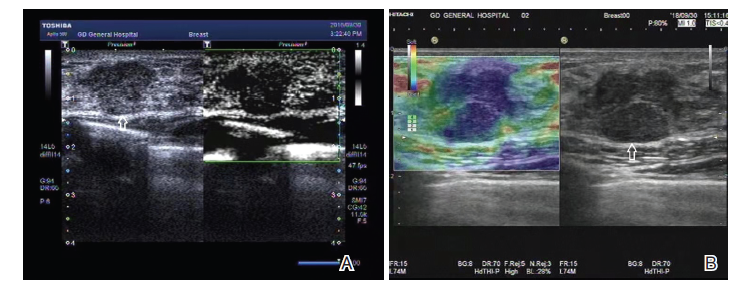

图2 乳腺癌mSMI及RTE表现

注:女性, 41岁。左侧乳腺发现低回声结节(箭头所指), 最大直径12 mm, 实性, 低回声, 形态规则, 边界清, 边缘尚清, 纵横比=1, 内部无钙化, 常规超声倾向于良性结节, ACR BI-RADS 4类。A. mSMI分型为Ⅴ 型; B. RTE为4分, 多模态超声成像评估为恶性结节, 经手术病理被证实为三阴性乳腺癌

Fig.2 mSMI and RTE manifestations of breast cancer

Note: Female, 41 years old. Hypoechoic nodules(indicated by arrow)in the left breast, maximum diameter 12 mm, solid, hypoechoic, regular shape, clear boundary, clear margin, aspect ratio=1, no internal calcification, conventional ultrasound tended to be benign nodules, ACR BI-RADS type 4. A. mSMI was classified as typeⅤ ; B. RTE was 4 points, malignant nodules were evaluated by multimodal ultrasound, triple-negative breast cancer was pathologically confirmed